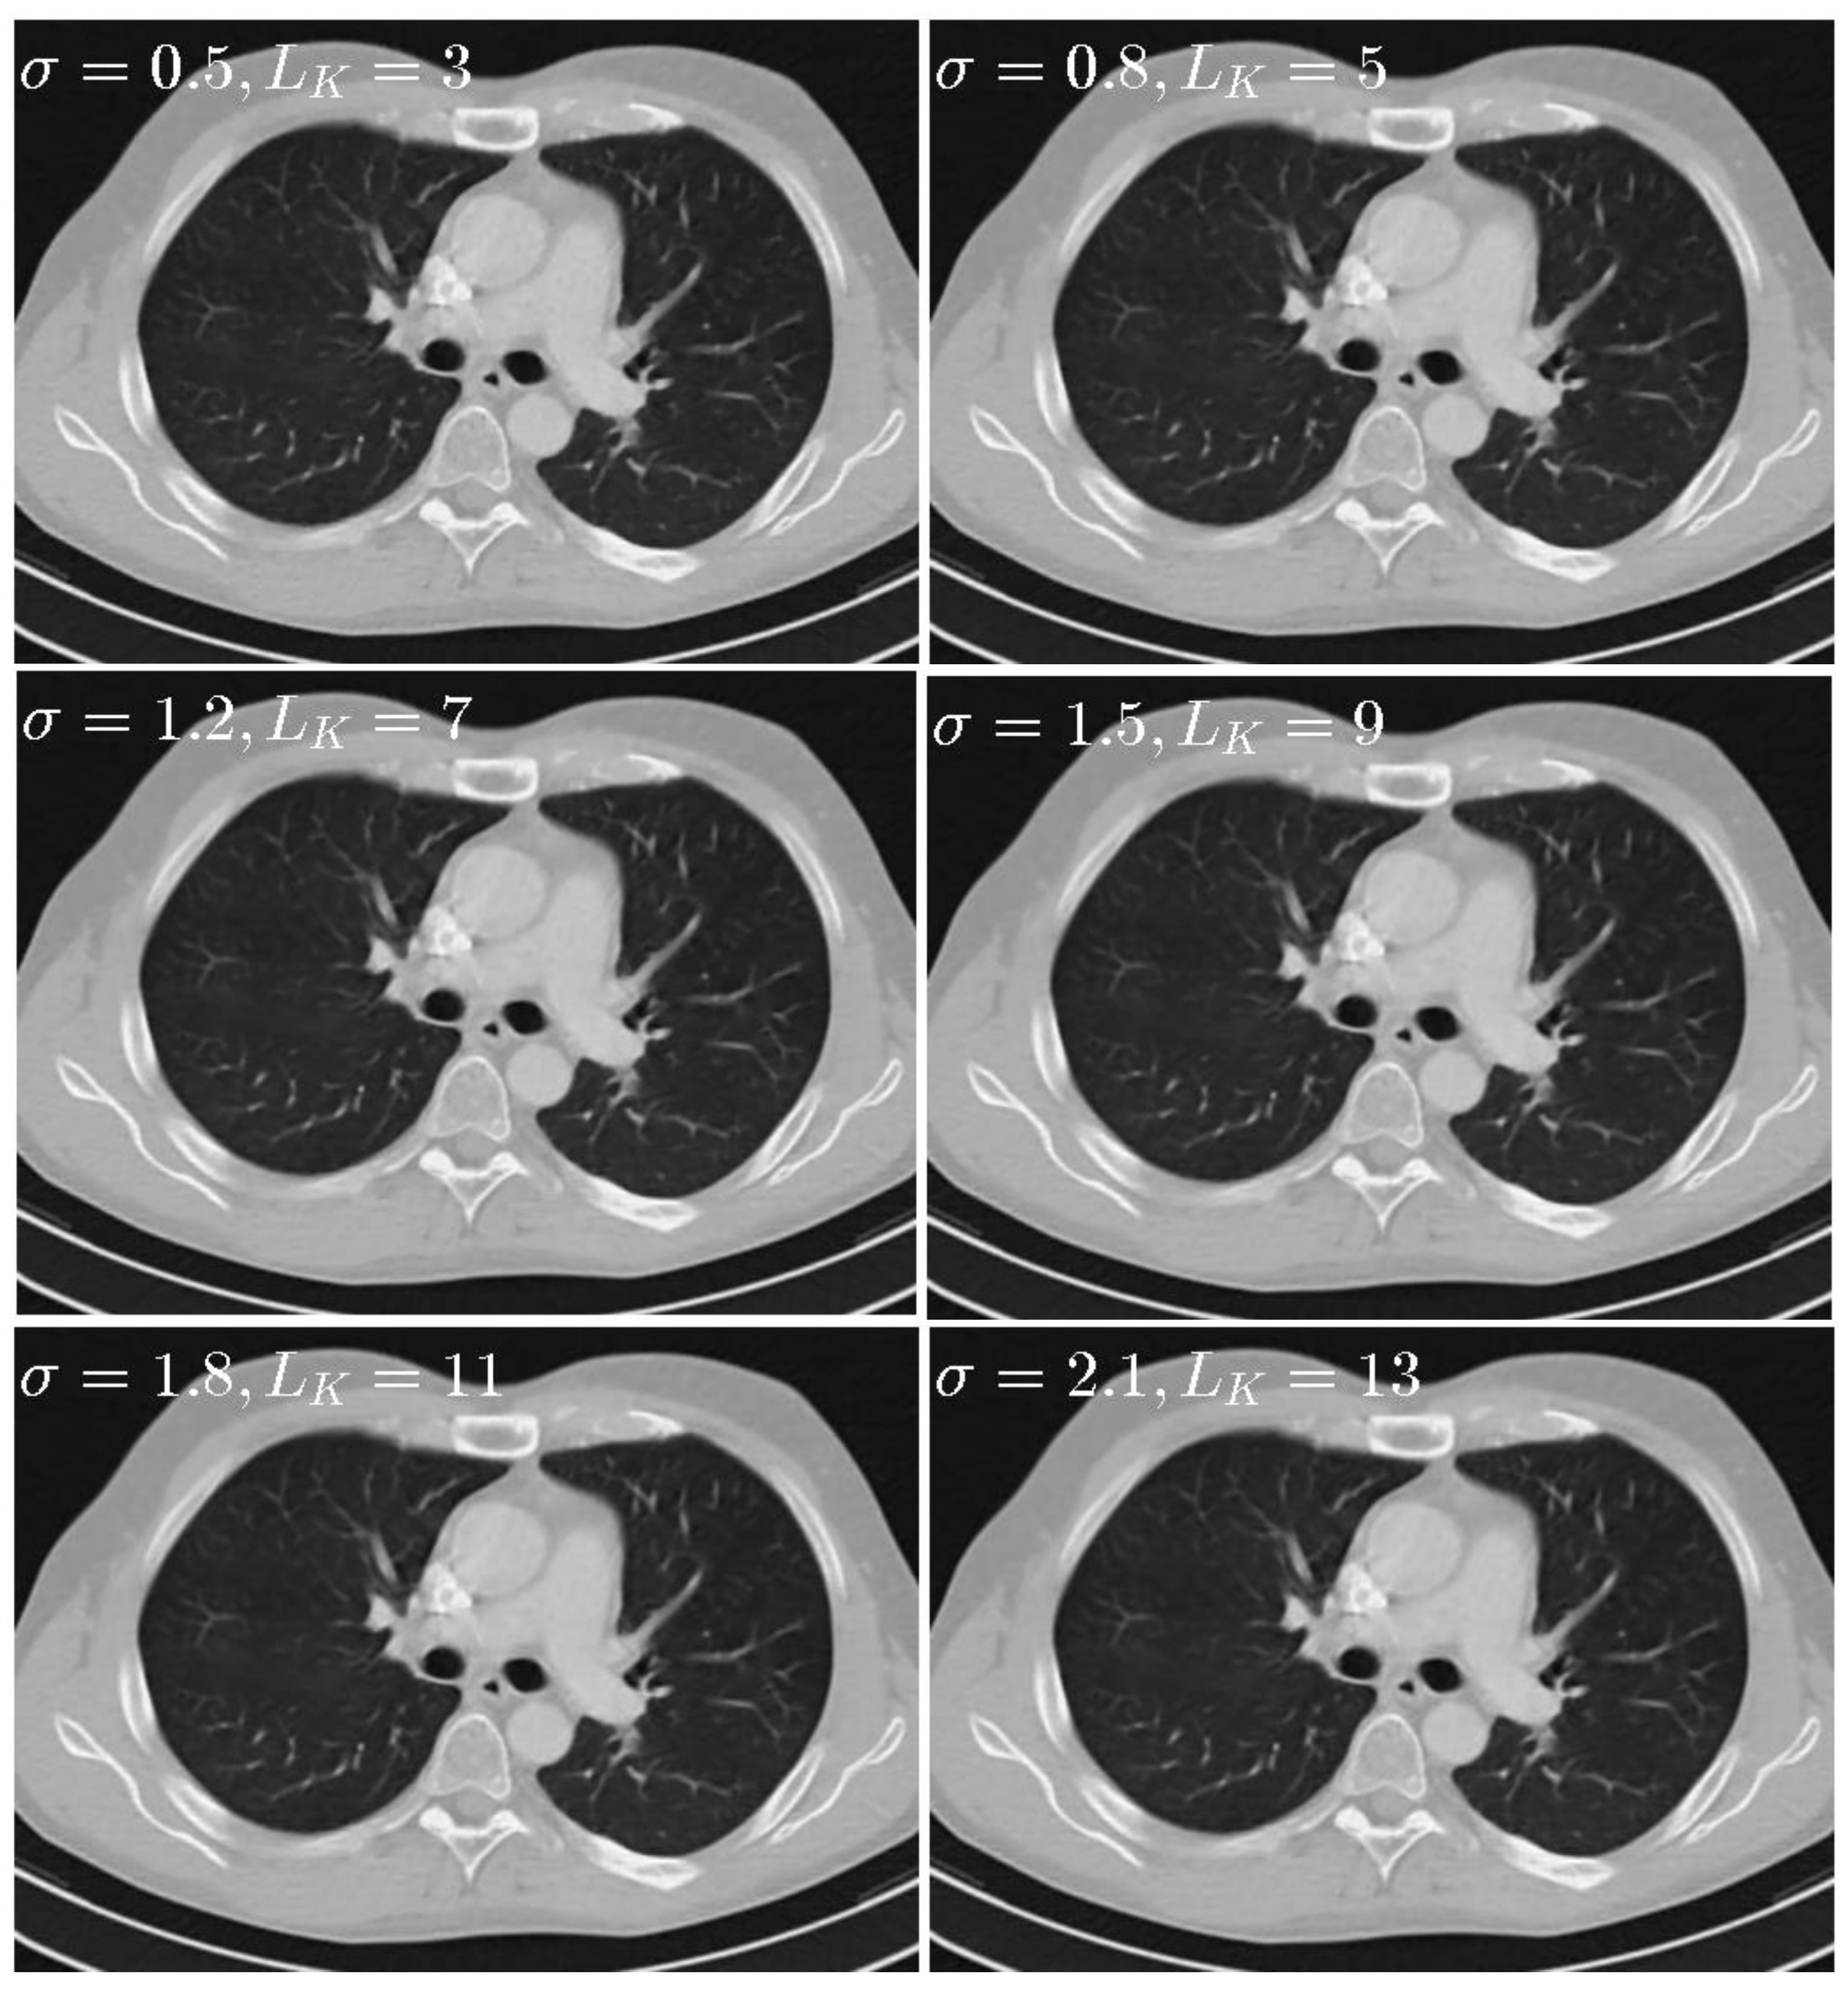

(2) Parameters σ and LK

When σ was set to 0.5, Gaussian kernel with 99.7% of its energy will be within three pixels, so LK and σ should be changed together instead of separately. To sense the impact of parameter σ and LK, six different sets of parameters including σ = 0.5 , L K = 3 , σ = 0.8 , L K = 5 , σ = 1.2 , L K = 7 , σ = 1.5 , L K = 9 σ = 1.8 , L K = 11 , and σ = 2.1 , L K = 13 are tested. The results are given in Figure 8. In addition, the quantitative results are given in Table 3. The results show that the performance of our proposed method is not quite sensitive to parameter LK and σ and that there are no noticeable difference for different parameters. To balance the performance and computational time, the σ is set to 0.5, LK is set to 3 in this paper.

Figure 8. Thorax images reconstructed by the SIR-STV1 method with respect to different σ and LK. The display window is [−1000, 667] HU.